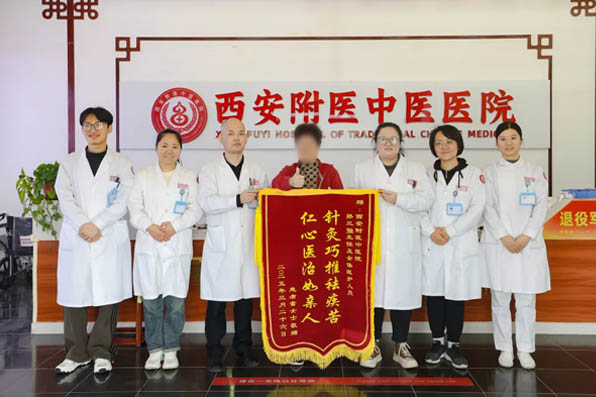

西安附医中医医院党支部正式成立